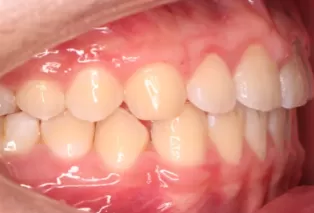

Intraoral photos after treatment